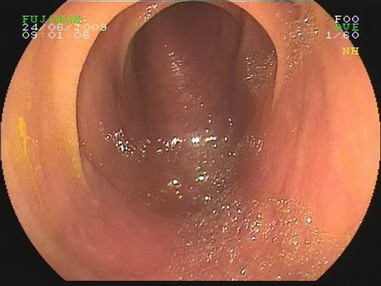

2009.6.24胃镜:

慢性浅表性胃炎,十二指肠淤滞症原因待查,肠系膜上动脉压迫综合症?(胃内可见胆汁样物反流,十二指肠球扩张,降部明显扩张,水平部远端似可见狭窄,持续充气肠腔不能打开。)